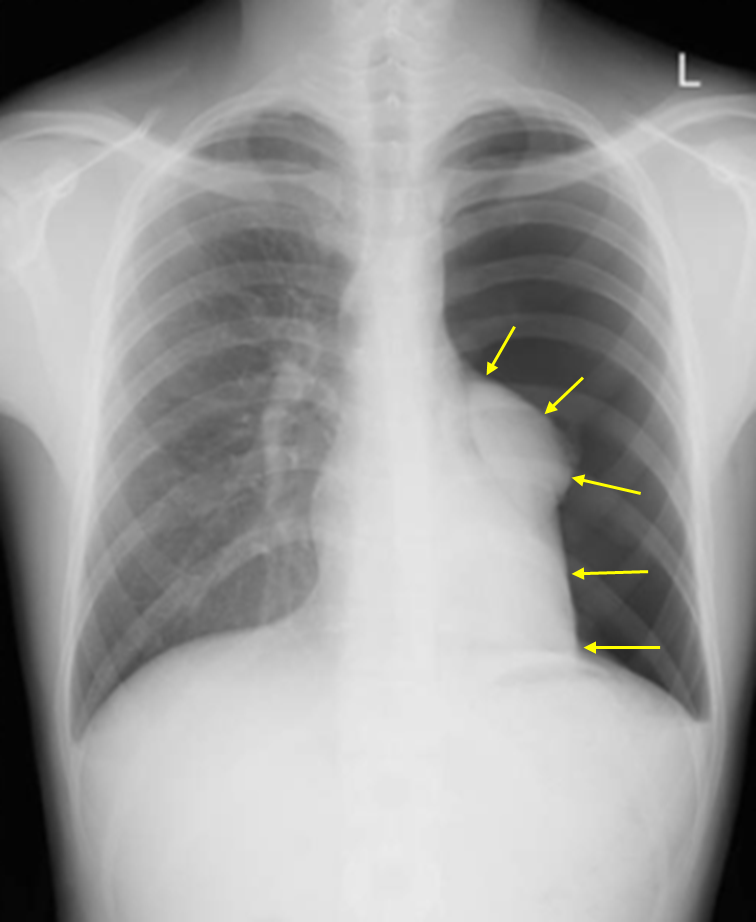

23세 남자가 1일 전부터 왼쪽 가슴이 아파서 병원에 왔다. 누웠다 일어나면 통증이 심해졌으며, 1시간 전부터는 숨이 찬다고 한다. 2년간 하루 1갑의 담배를 피웠다고 한다. 혈압 110/70 mmHg, 맥박 76회/분, 호흡 18회/분, 체온 36.4℃이다. 왼쪽 가슴에서 호흡음이 들리지 않는다. 가슴 X선 사진이다. 진단은?

Img | CXR: 좌측 폐혈관 음영 소실 |

담배 피는 20대 남자가 왼쪽 가슴 통증, 왼쪽 호흡음 소실이 있고 CXR에서 좌측 폐혈관 음영이 안 보이므로 기흉으로 진단한다.

• CXR에서 좌측 폐의 bronchovascular marking이 안 보이므로 기흉으로 진단한다.

검사소견 | • CXR: Pleural line 보임, vascular marking이 보이지 않음 |